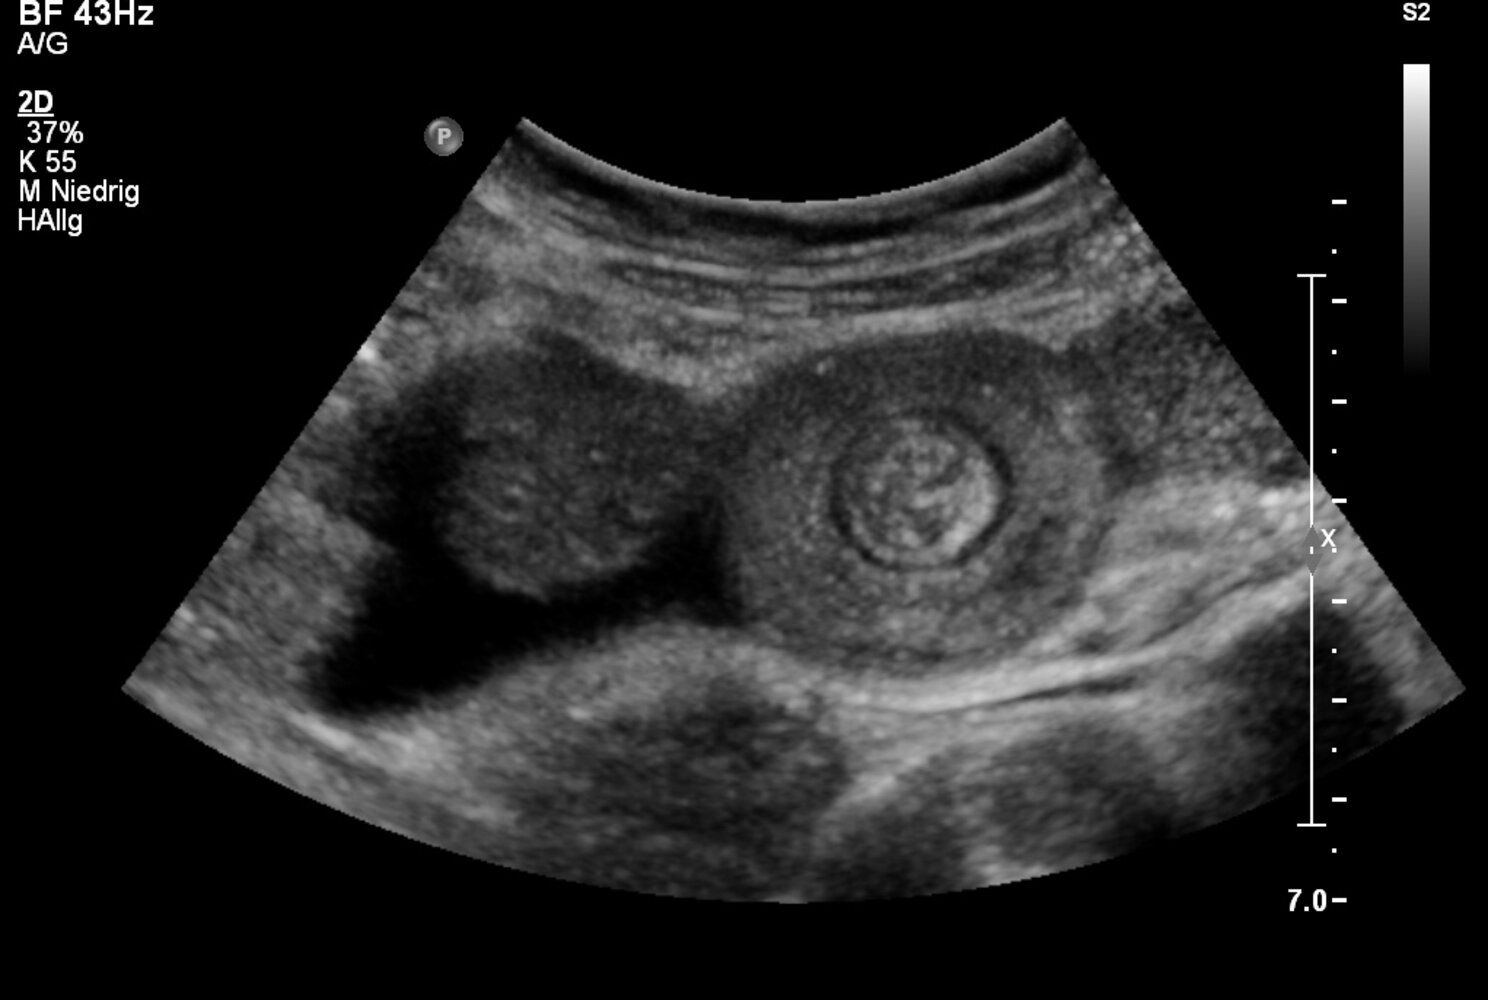

• “Target sign” on ultrasound

• Ultrasound may show small bowel obstruction (donut sign).